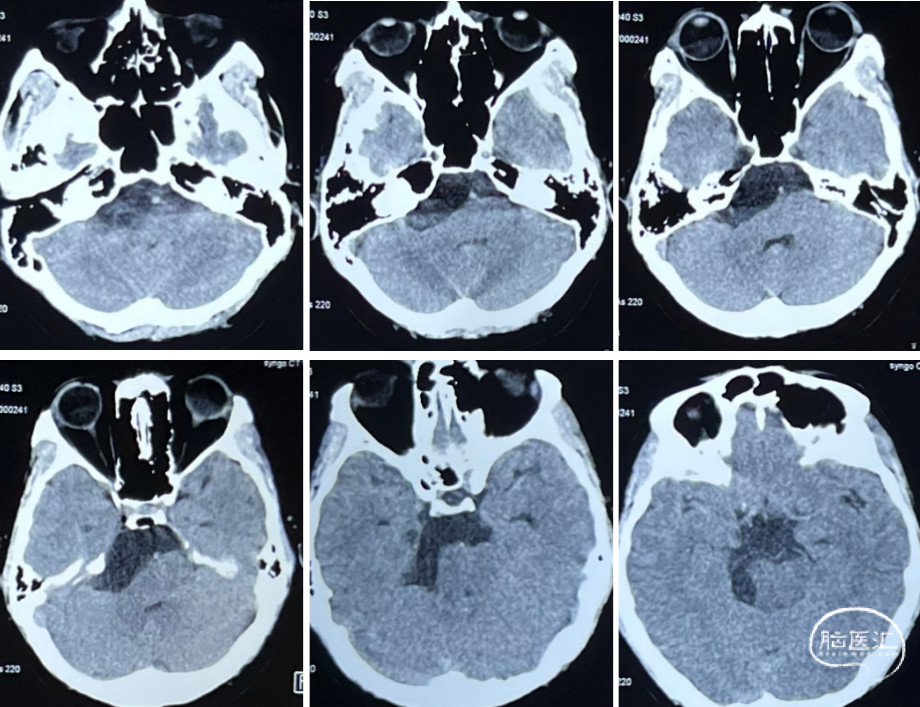

术前CT